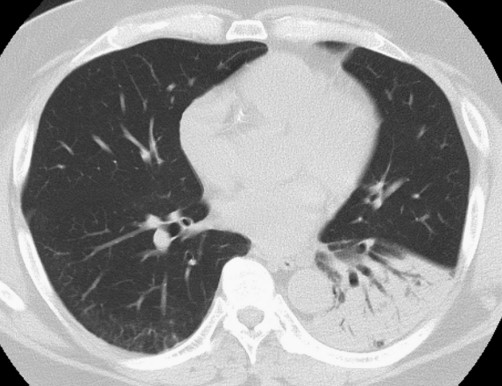

患者體格檢查無明顯異常。血液檢查顯示C反應(yīng)蛋白水平升高,1.80 mg/dL;天冬氨酸轉(zhuǎn)氨酶輕度升高,55 U/L;丙氨酸轉(zhuǎn)氨酶升高,58 U/L。其他指標(biāo)無明顯異常。血清β-D葡聚糖、人類免疫缺陷病毒(HIV)血清學(xué)和結(jié)核感染T細(xì)胞檢測(T-SPOT.TB)檢查均為陰性。高分辨率CT掃描顯示左肺下葉實(shí)變伴空氣支氣管征(圖1)

圖1 高分辨率CT掃描顯示左肺下葉實(shí)變伴空氣支氣管征